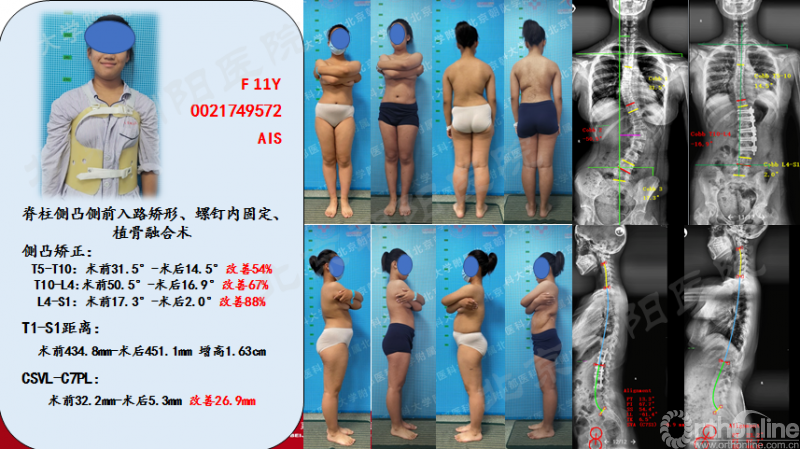

患者11岁青少年女性,诊断为Lenke 5C型AIS,T10-L4 Cobb角50.5°、T5-10 Cobb角31.5°,主弯顶椎为L1,融合范围选择为T1-L3。

患者术前术后大体照及X片对比